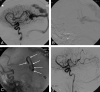

Background and purpose: To report the initial experience by using a new liquid embolic agent (Onyx) for embolization of brain arteriovenous malformations (AVMs).

Methods: Between May 2000 and December 2005, 44 patients with brain AVMs were embolized with Onyx. There were 18 women and 26 men with a mean age of 42.4 years (median 44, range 14-71 years). Clinical presentation included seizures in 26 patients (59%), hemorrhage from the AVM in 13 patients (30%), subarachnoid hemorrhage from a concomitant aneurysm in 3 patients (7%), visual disturbances in 1 patient (2.3%), and in 1 patient (2.3%) the AVM was an incidental finding. Mean estimated size of the AVM was 3.9 cm (median 4, range 2-7 cm).

Results: In 44 patients, 52 embolization procedures were performed with 138 feeding pedicles embolized, ranging from 1 to 7 per patient. Average estimated size reduction was 75% (median 80%, range 40%-100%). Total obliteration was achieved in 7 AVMs (16%), and partial embolization was followed by surgery in 10 patients and by radiosurgery in 20 patients. Complications occurred in 6 patients, leading to death in 1 patient (mortality 2.3%) and to permanent disability in 2 patients (morbidity 4.6%).

Conclusion: Onyx is feasible and safe in the embolization of brain AVMs. Complete obliteration can be achieved in small AVMs. Large AVMs can be adequately reduced in size for additional surgical or radiosurgical treatment.